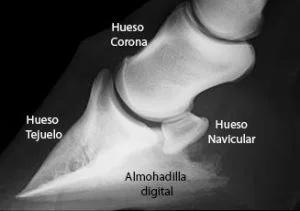

En primer lugar vamos a ver la composición exterior e interior del casco equino de forma bastante resumida pero suficiente para entender la importancia de su cuidado y mantenimiento (Ver diagrama adjunto).

Las anteriores estructuras forman una “cápsula” (el casco equino) que protege una delicada estructura interna y ósea. Las mismas estan formadas de las siguientes partes (Ver segundo diagrama):

Hueso tejuelo

Hueso navicular

El hueso corona (solo la parte inferior está dentro del casco)

Almohadilla digital (cojín plantar): Es de material elástico, cartilaginoso. Tiene la función absorver el choque y bombear la sangre a través de sus plexos venosos.

Corion: Es una estructura vascular (arterias y venas) que rodea los huesos, produce las áreas intertubulares y fabrica la parte interna del casco.

Cartilagos laterales: Actúan como resortes, almacenando y liberando energía durante el movimiento de las extremidades.

Plexos venosos: Son una red de vasos sanguineos que junto con el corion nutren al casco desde su interior.